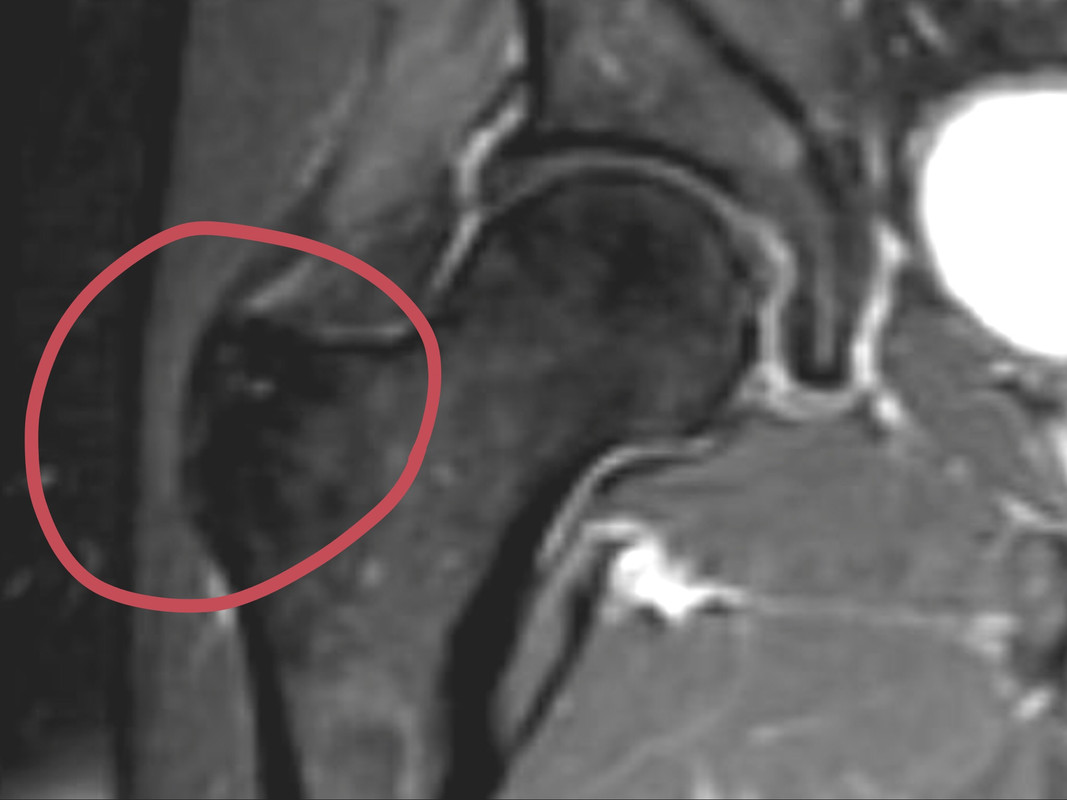

When I showed this area to my GP a few years ago, he said, “that doesn’t makes sense that it would be a arthritis area, it doesn’t get any wear and tear”. But it does get inflammation! You can see the enthesitis in the MRI, I believe, the white area, just in front of the part that looks charred with a blow torch…

I went to my Pain doctor today, he gave me a cortisone shot in each hip At the bursa, (see photo of Charred spot) really is a nice doctor. He was asking how much the Tramadol helps my pain, I said 30% on the back pain but also great as a anti- anxiety drug, little known bonus about this pain medication! I said the 15 Norco help some for breakthrough Pain, but also make it less impactive. Since I space out the Norco over roughly 4 day periods, depending on the pain, no real dependency build up. With PsA, SFN, OA, DISH, DDD, EM and other acronyms I cannot think of right now, it sometimes makes “a Perfect storm” for pain and anxiety.